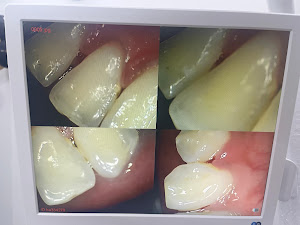

Welcome to our gallery

See how our company transforms ideas into reality. This gallery is a visual testament to our work and achievements.